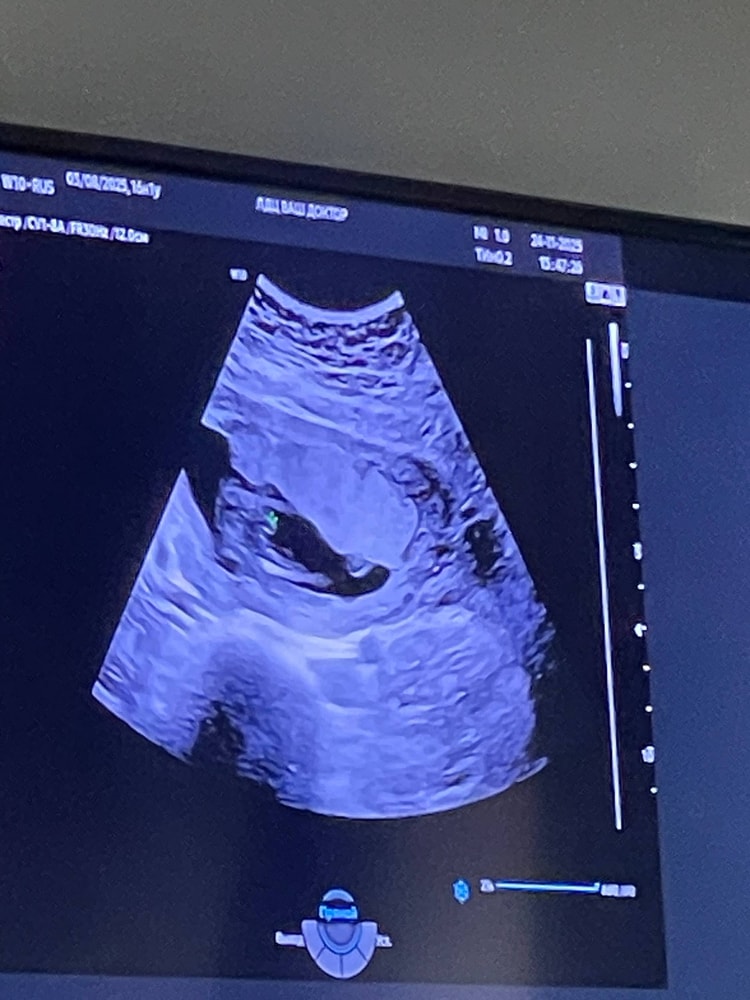

17 недель. Было уже прям понятно